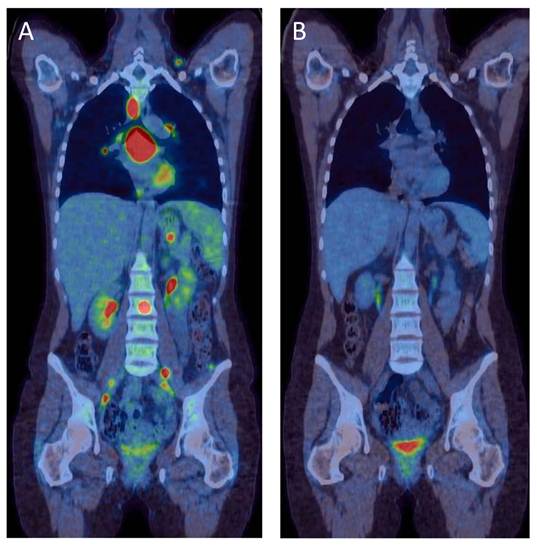

PET is inherently a quantitative technique, meaning that the scanner measures radioactivity concentrations, not merely isotopic decays. The quantitative properties can be utilized in many different ways and is the foundation of the use of PET in biomedical research.[6] In the clinical routine situation, quantitation provides an opportunity to compare tumor tracer uptake in serial measurements, for example before and after treatment. Assuming that a sufficient decrease in FDG uptake early after treatment reflects a similar and sustained reduction in tumor growth, this technique could be used as a biomarker of treatment effect. Recent years have seen a strong interest in investigating the potential clinical utility of this biomarker approach to serial imaging.[7] The most obvious example of success is in the evaluation of lymphoma treatment.[8] Malignant lymphomas are characterized by a very high FDG uptake and, similar to the case of lung cancer, FDG-PET/CT often upstage patients because more lesions are detected than with any other approach. Modern treatment is highly effective and has improved survival greatly, but the lumpy lymphoma lesions often heal with scar formation. These scars consist of fibrous tissue, disappear slowly and cannot be distinguished from residual malignancy with CT or MRI alone. When the lymphoma patient is scanned after treatment, a residual lump without any FDG uptake is a prognostically excellent sign, while elevated FDG uptake signals remaining viable tumor with minimal likelihood of cure unless treatment is changed.[8] An example of the sometimes dramatic changes in tumor FDG uptake after successful treatment can be seen in Figure 2.

Figure 2

FDG-PET/CT for staging and treatment evaluation in lymphoma. Combined coronal [18F]-FDG PET/CT images from a 25-year old woman, who was diagnosed with aggressive Non-Hodgkins Lymphoma. Prior to PET/CT the patient was known to have disease in the neck and mediastinum. The left image was obtained before treatment and showed extensive growth of tumors not only in the neck and mediastinum, but also in abdominal lymph nodes, bone marrow, liver and spleen. This image dramatically changed the disease stage and the associated treatment. The image to the right shows the same view after three courses of a standardized chemotherapy regime, typically given in 8 courses. The mediastinal lumps remain visible on CT, termed ”partial anatomical remission”, but neither these lumps nor any of the previously diagnosed lymphoma locations show pathological FDG uptake, a pattern of findings termed ”complete metabolic remission”. This finding after treatment is highly predictive of treatment success without any need of therapy changes. On the other hand, remaining FDG uptake in any of the known lumps is associated with a high likelihood of recurrence.

Serial FDG PET for treatment evaluation as an early biomarker for outcome has been investigated in several cancer types, but no specific protocols have so far been established in clinical routine with international consensus, apart from lymphoma. Even for lymphoma, the best documented disease in which treatment evaluation using PET is considered relevant, multicenter studies are needed to optimize and refine the protocols. Defining optimal protocols for other malignancies is an area of intense interest and research, by some considered crucial for future drug development.[7, 9-11]